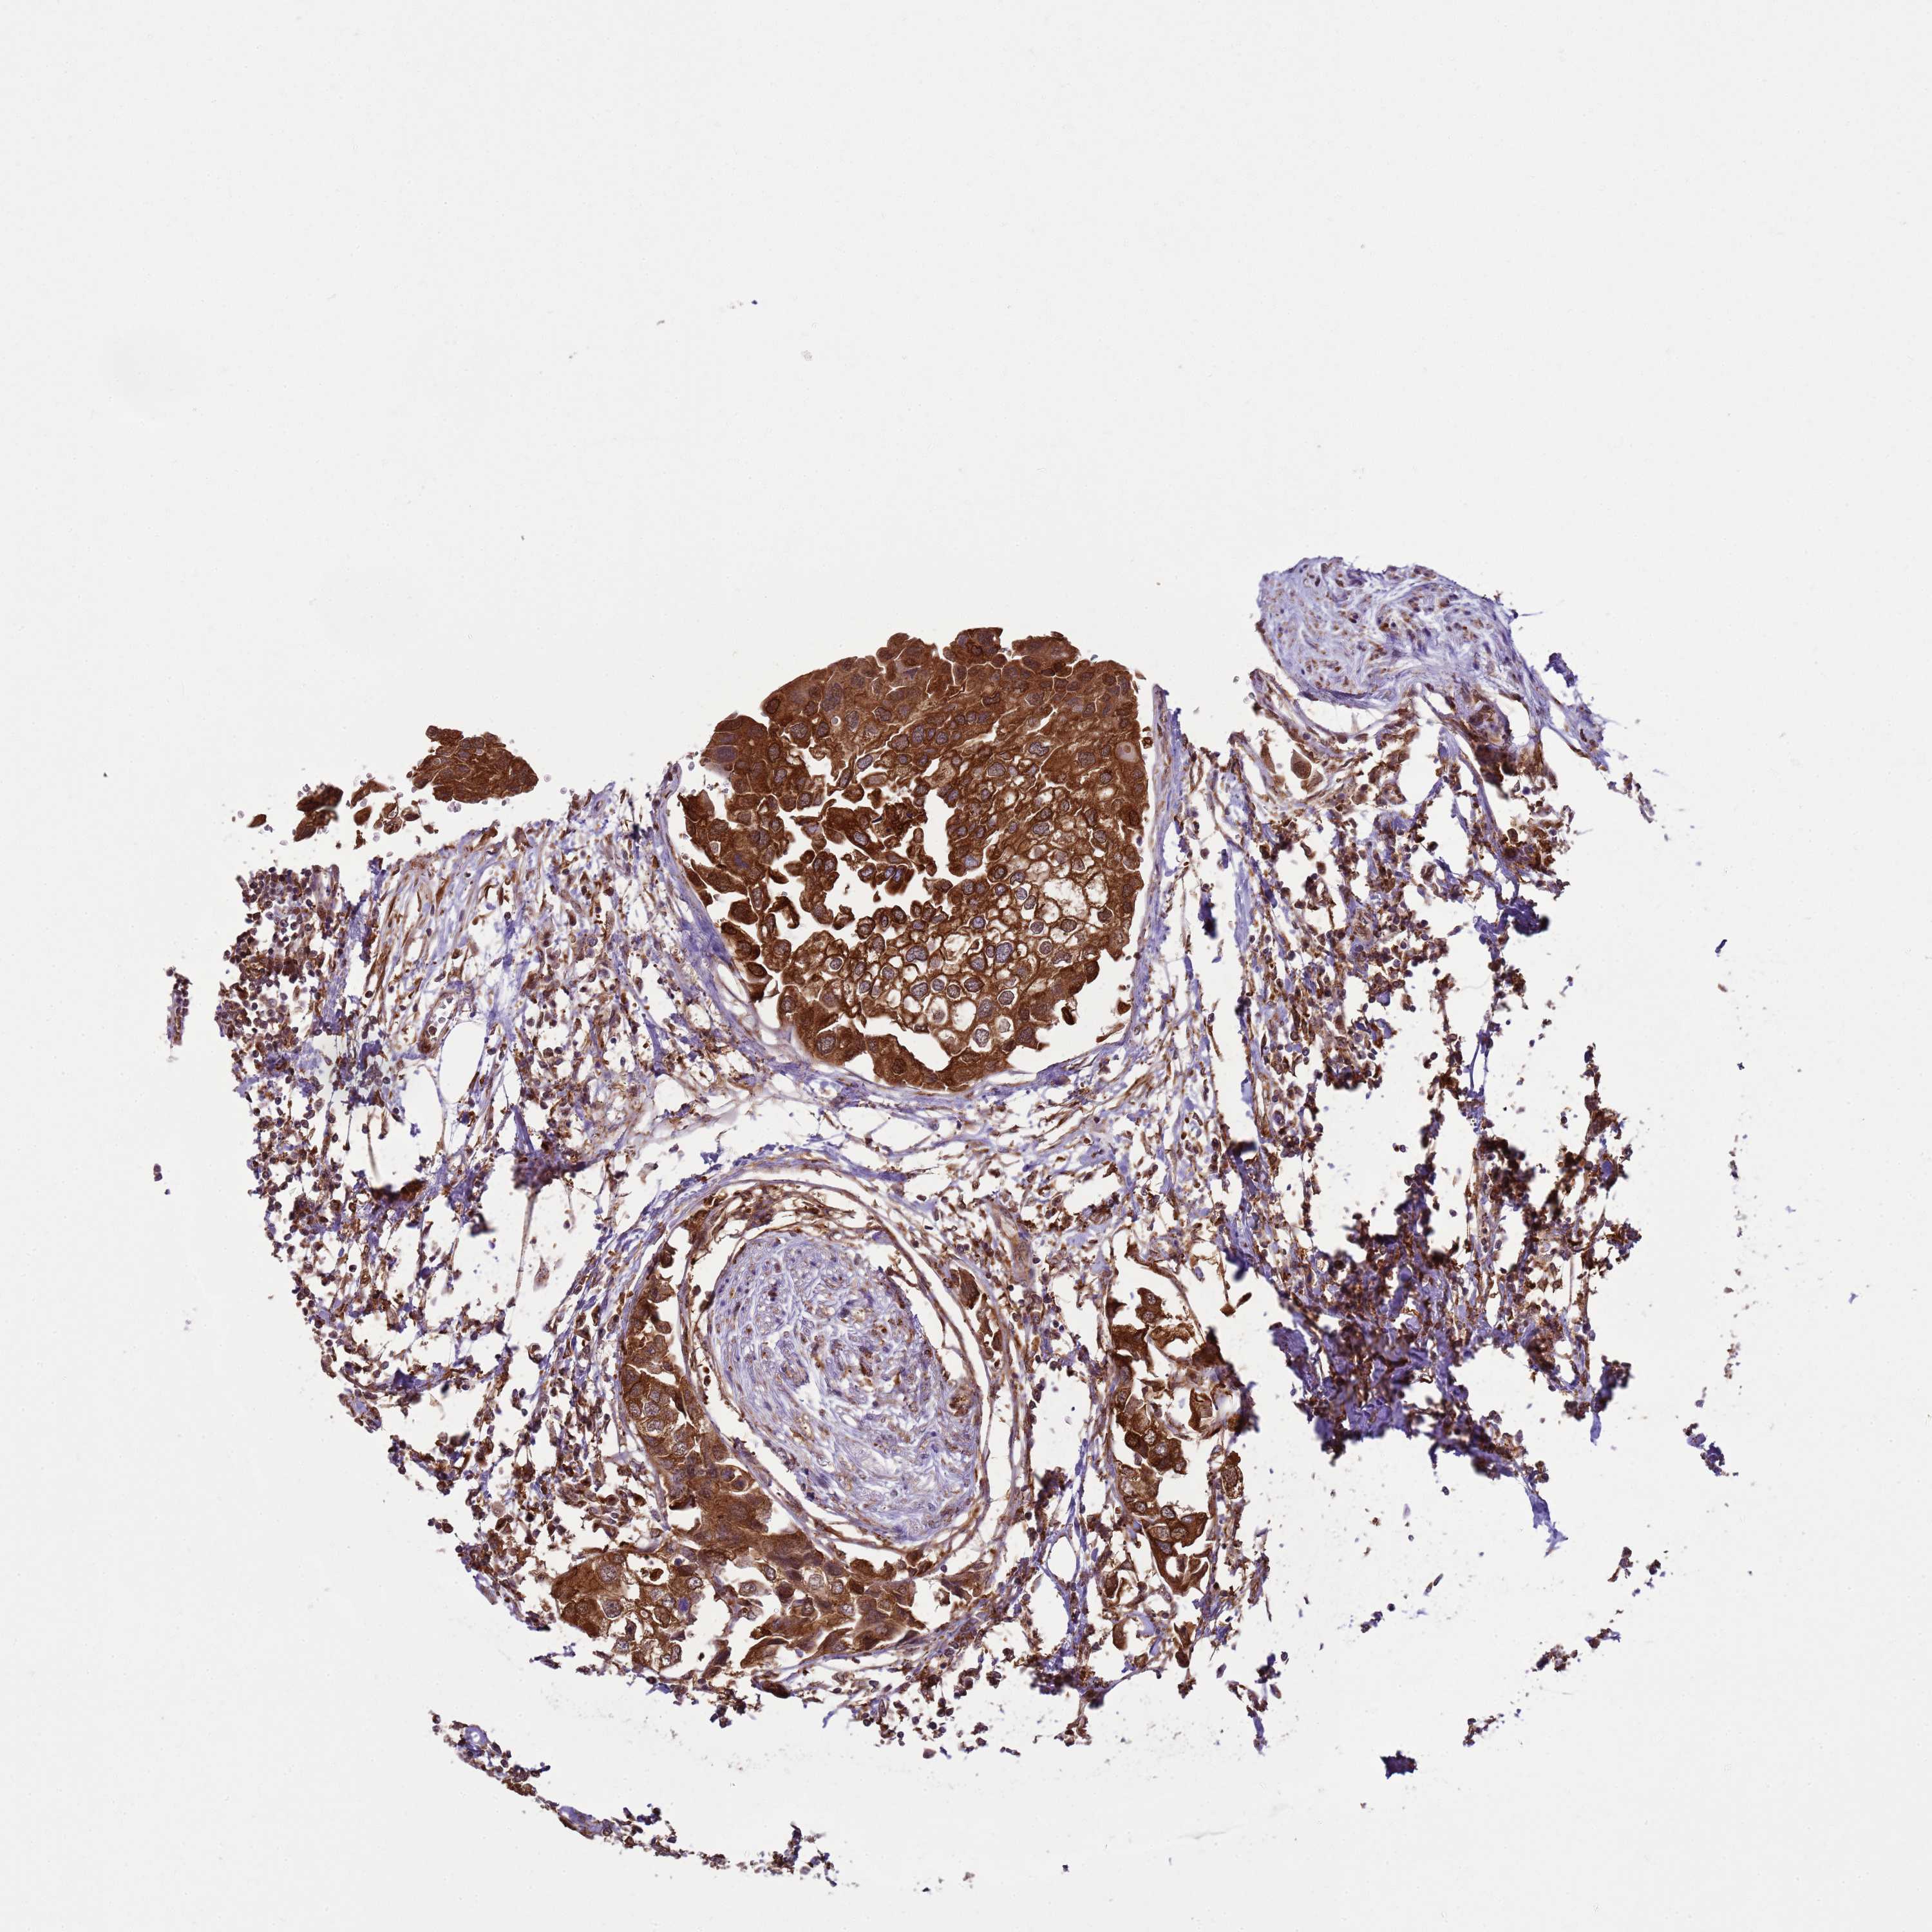

UROTHELIAL CANCER - Protein expressioni

A mouse-over function shows sample information and annotation data. Click on an image to view it in a full screen mode. Samples can be filtered based on level of antibody staining by selecting one or several of the following categories: high, medium, low and not detected. The assay and annotation is described here.

Antibody stainingi

Antibody staining in the annotated cell types in the current human tissue is reported as not detected, low, medium, or high, based on conventional immunohistochemistry profiling in selected tissues. This score is based on the combination of the staining intensity and fraction of stained cells.

Each image is clickable and will lead to virtual microscopy that enables deeper exploration of all samples and also displays staining intensity scores, fraction scores and subcellular localization as well as patient and tissue information for each sample.

Antibody HPA045918

Staining

High

Medium

Low

Not detected

Intensity

Strong

Moderate

Weak

Negative

Quantity

>75%

75%-25%

<25%

None

Location

Nuclear

Cytoplasmic/membranous

Cytoplasmic/membranous,nuclear

Urothelial carcinoma, High grade

Urothelial carcinoma, Low grade

Urothelial carcinoma, NOS